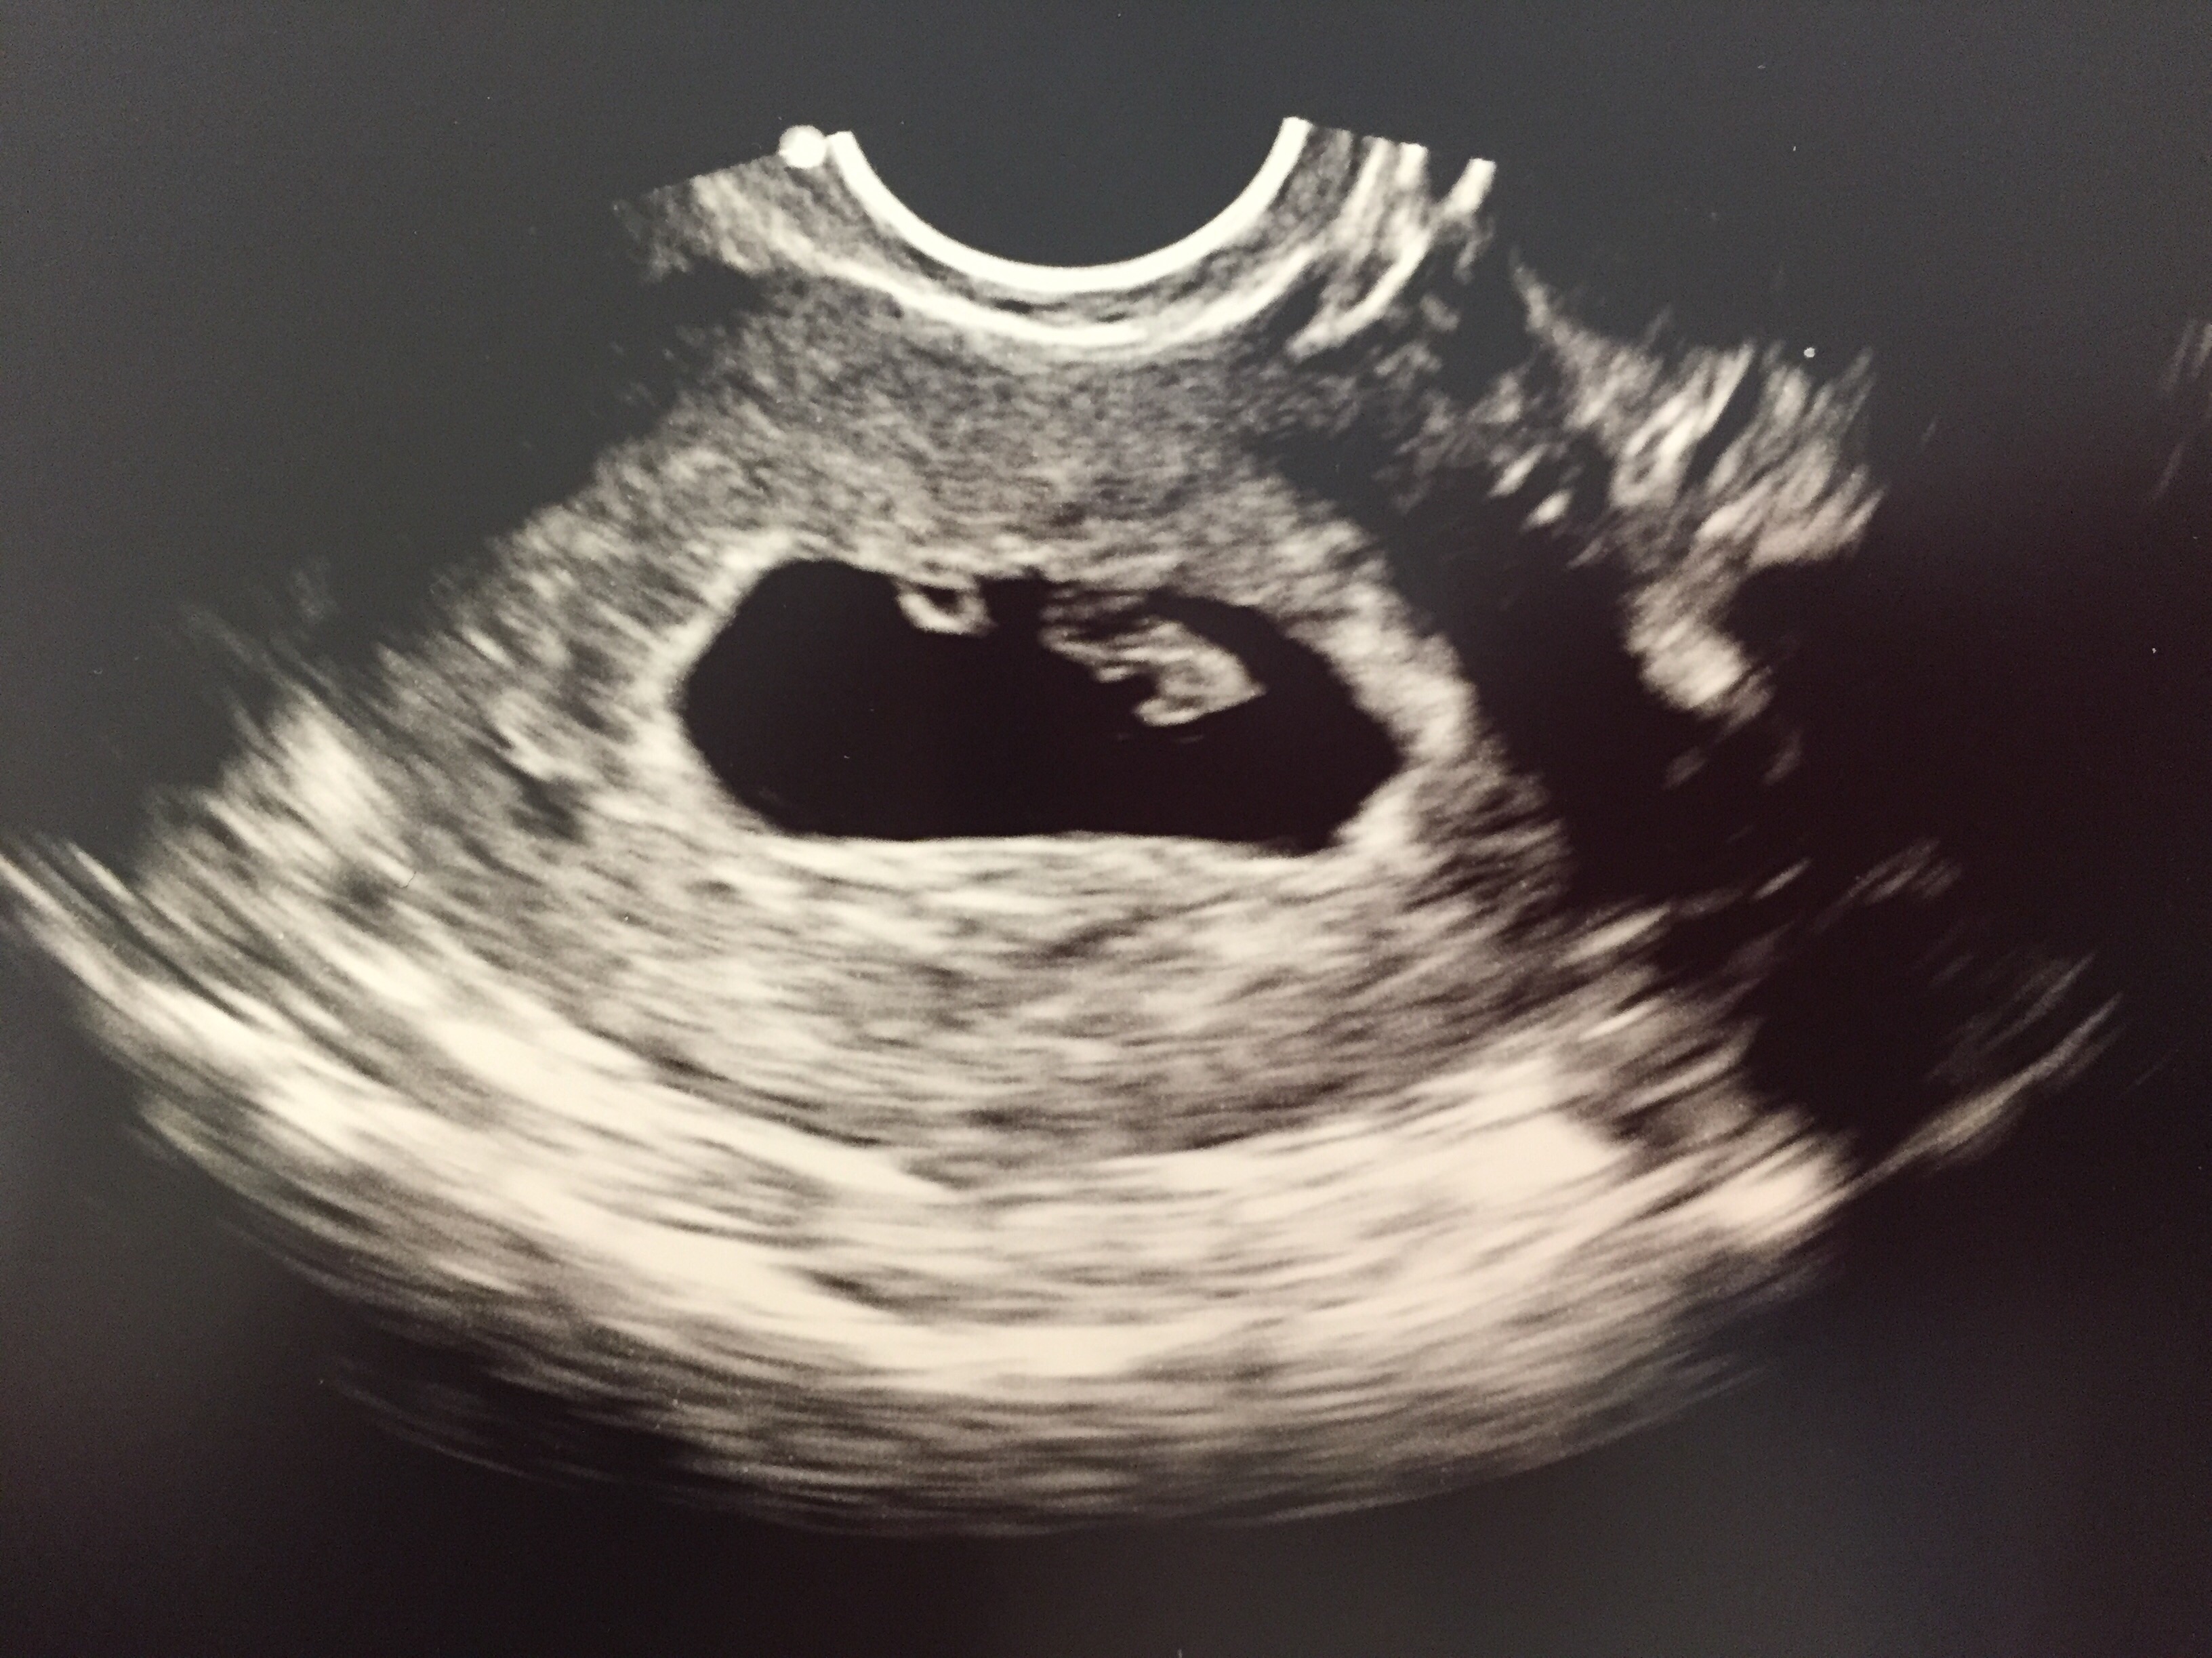

U/S #1, 12/23: gestational sac, possible heartbeat

U/S #2, 12/30: HEARTBEAT! 128bpm, measuring right on at 7w EDD: 8/19/2015

U/S #3, 1/9: BPM in the 180s, IT'S HAPPENING!!!